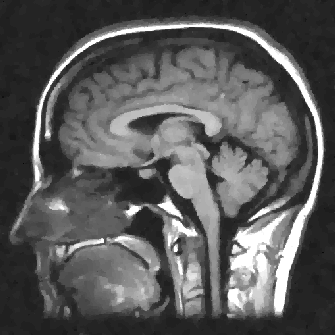

We display the noisy image and the reconstructed images from these three denoising methods in Fig. 8 111 Image retrieved from http://radiopaedia.org/ by Frank Gaillard.. To better understand the performance, we zoom in the selected part of the image and display them in Fig. 9.

Refer to caption

(a) Noisy

(b) Anisotropic TV

(c) TFV, α=1.3𝛼1.3\alpha=1.3

(d) TV-TFV, α=1.3𝛼1.3\alpha=1.3

Figure 8: Denoising results for models with different regularities. Here α𝛼\alpha denotes the fractional order of derivative in TFV model.

We observe that the anisotropic TV suffers from the staircase artifact due to the fact that the TV is local operator. On the other hand, the reconstruction with TFV regularity has blurry effect on the edges. This is not surprising because the TFV is a non-local method and it is less edge sensitive than TV. Instead, the TV-TFV regularity avoids such artifacts and has a better reconstruction of both the edges and the overall image.

We also present the numerical results of different performance measurements in Table 3. The TV-TFV regularity shows better results in such measurements as well.

Table 3: Numerical results for denoising with different regularities.

\hlineB3 Model psnr snr rela_err

\hlineB3 Noisy 20.9199 6.0853 0.3914

TV 31.0007 16.1661 0.1226

TFV 31.6910 16.8565 0.1133

TV-TFV 32.1948 17.3602 0.1069

\hlineB3